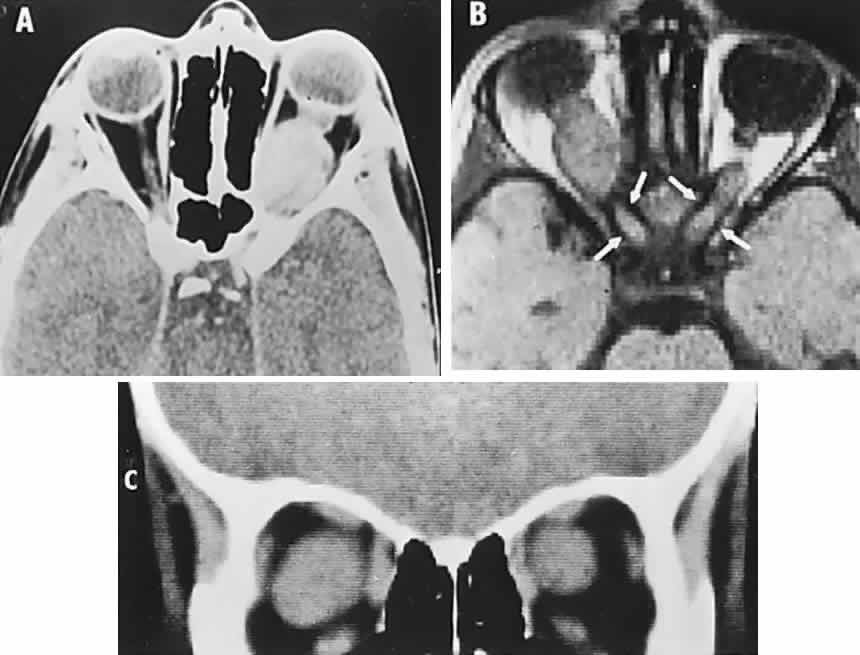

The “neurophakomatoses” are a diverse group of disorders nosologically related by the presence of hamartomatous lesions, and, indeed, the term “hereditary hamartomatosis” is a more accurate description. However, whereas neurofibromatosis, tuberous sclerosis, and von Hippel-Lindau disease are transmitted with irregular dominance and considerable variation in penetrance, no hereditary basis of Sturge-Weber or angio-osteohypertrophy (Klippel-Trenaunay-Weber) syndrome has been established.

A hamartoma is a tumor of anomalous origin composed of elements normally present in the tissue in which it originates and with a limited capacity for proliferation. The following tumors may be classified as hamartomas: (1) in neurofibromatosis: optic gliomas (see Chapter 6), neurofibromas, and ganglioneuromas; (2) in tuberous sclerosis: retinal and cerebral astrocytomas, cutaneous angiofibromas (“adenoma sebaceum”), rhabdomyomas, and leiomyomas; (3) in von Hippel-Lindau disease: hemangioblastomas of the cerebellum and retina (including optic nerve head) and renal hypernephromas or cysts; (4) in Sturge-Weber disease: facial and choroidal cavernous hemangiomas and meningeal angiomatous malformations; and (5) in Klippel-Trenaunay-Weber syndrome: cutaneous nevi, visceral and limb hemangiomas, and orbitofacial venous varices.

If all disorders with neurocutaneous manifestations are considered, the term phakomatoses (Greek, phakos, “spot,” “birthmark”) is appropriate, and the catalog of “related” disorders becomes cumbersome. “The Phakomatoses,” Volume 14 of Vinken and Bruyn's Handbook of Clinical Neurology, is extraordinarily complete and serves as a source of detailed clinical descriptions of these diseases.146 Syndromes characterized by vascular hamartomas, that is, retinal-cerebellar angiomatosis (von Hippel-Lindau), and other angiomatous malformations, are discussed in Volume 2, Chapter 17.